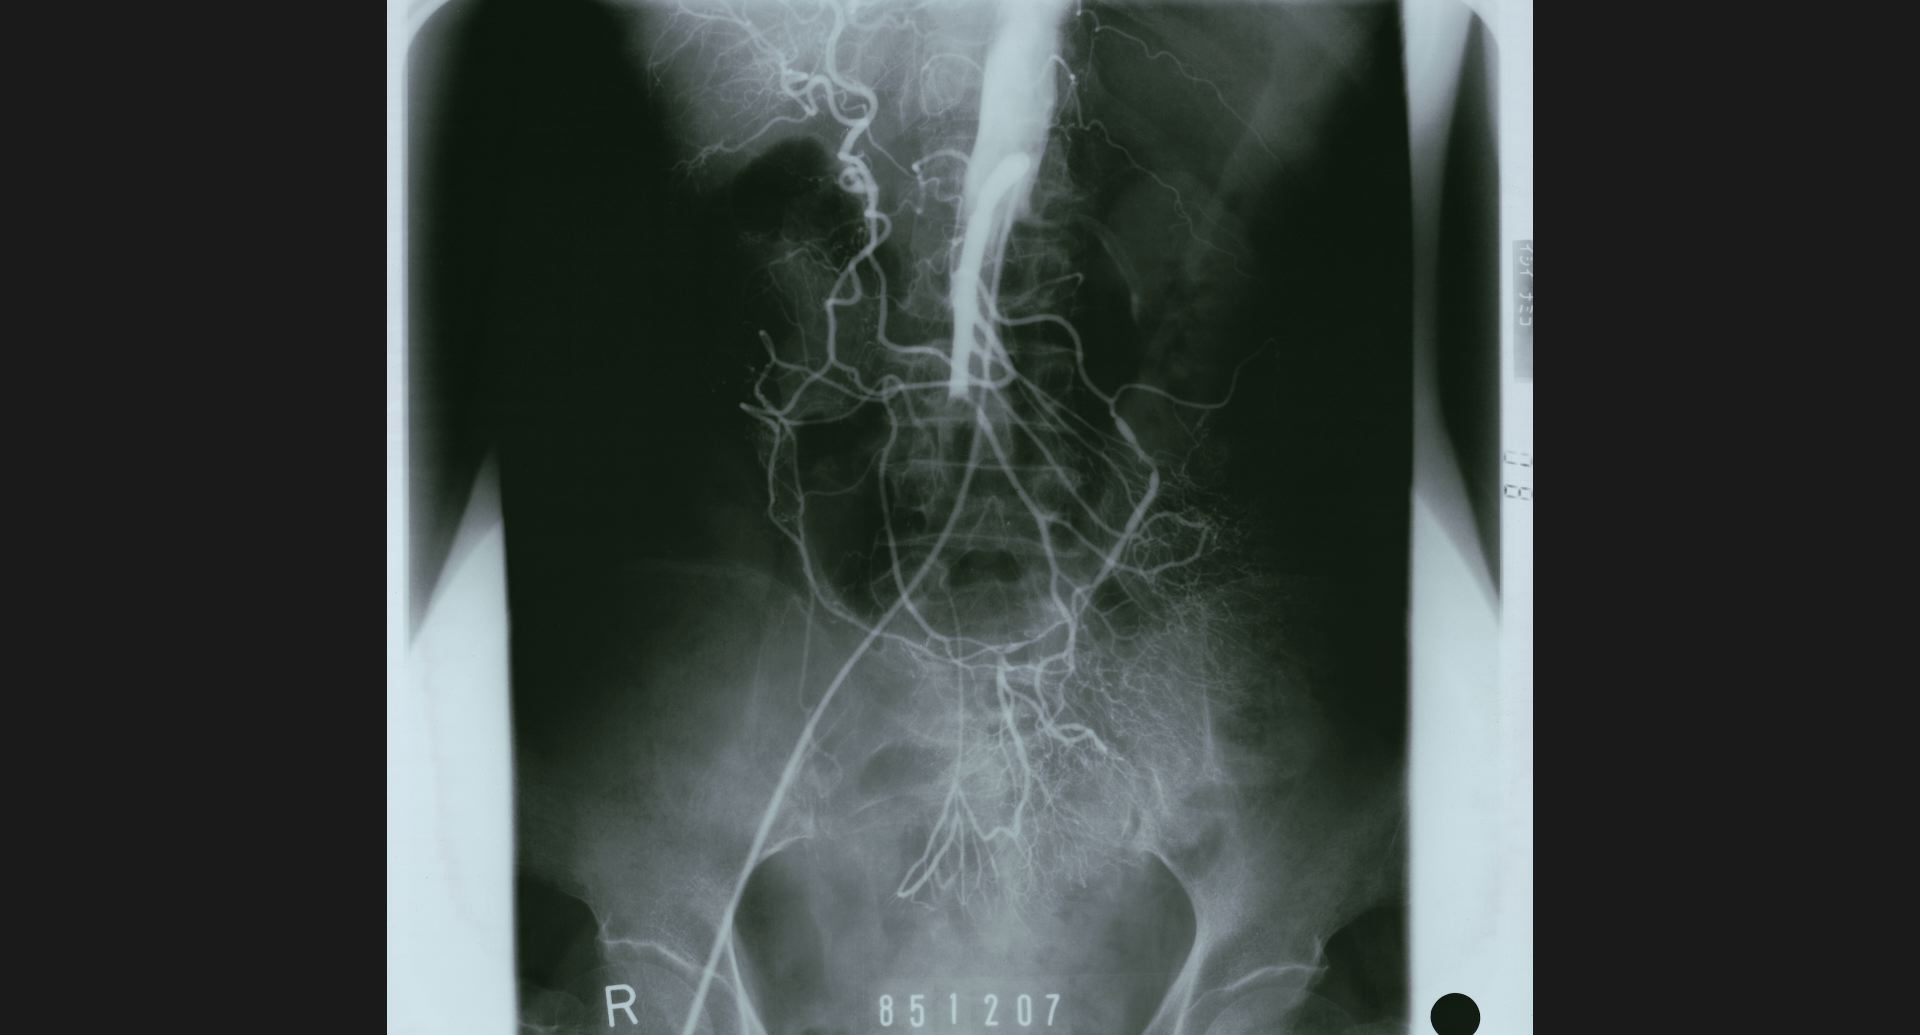

:Aortic aneurysm (DSA)aneurysm。正常部との境界。

fig.14(77KB)